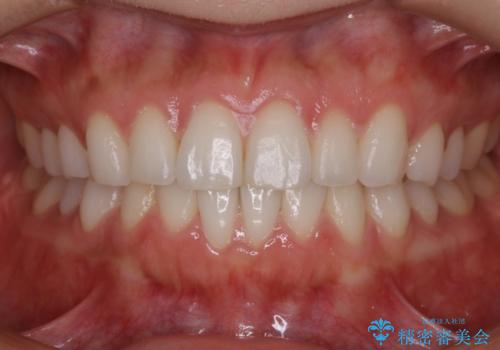

非抜歯でも劇的変化 インビザライン矯正治療

歯のガタつきを治すため矯正治療を希望。審査の結果、非抜歯での矯正が可能であるという見通しが立ったためインビザラインによる非抜歯矯正治療を行った。

歯を並べるスペースを作るために、歯の遠心移動と歯列の拡大、歯自体を少しだけ小さく削る(IPR)という方法を複合的に組み合わせて配列を行いました。遠心移動用のゴムかけにはマイクロインプラントという小さいネジを用いて骨に直接固定源を求めました。